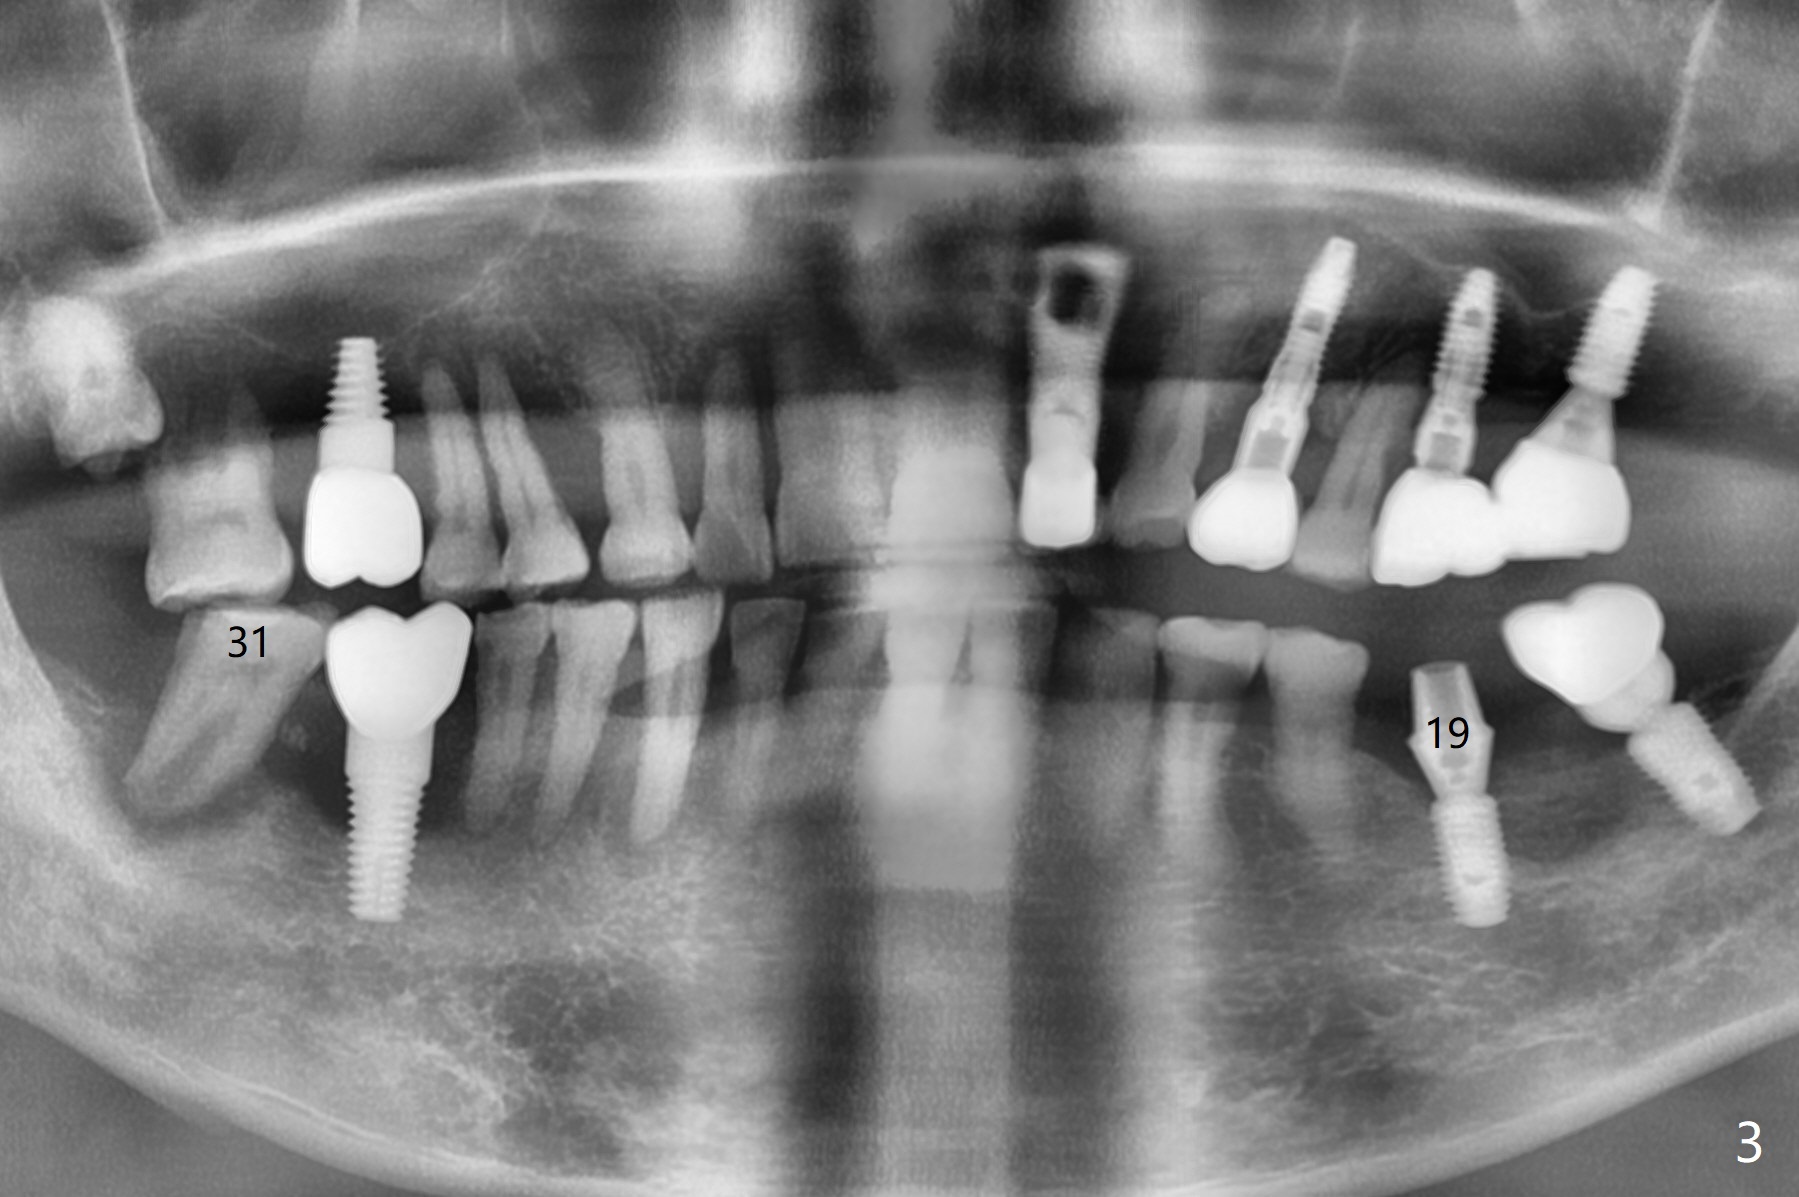

A 67-year-old man returns for periodic exam and #19 impression (Fig.3), which is impossible because there is open bite on the left (Fig.1 *). The latter is related to several periodontal abscesses (supraeruption, Fig.1,2). His chief complaint is mobility of #31 (Fig.3,4). Due to severity of infection, #31 is extracted with bone graft retained by Titanium-Reinforced Membrane (Cytoplast, Fig.5 T). PTFE suture is used. It is easy to tie knots with this non-resorbable (absorbable) suture. The Titanium-Reinforced Membrane exposes 1.5 months postop (Fig.6), which makes its removal easy (Fig.7). In fact the patient is pre-diabetic.